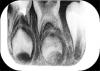

Как итог - не болит, но кусать ребенок на него боится, при сравнительной перкуссии/вроде так называется стучали вначале по 4 потом по 5 оба рядом на нижней челюсти/ на 4 не беспокоит, жалуется только на 5. Сделали снимок -прикрепляю, вообщем после снимка все в сомнении 5 ли реально беспокоит ребенка.

2. Есть ли по снимку какие то замечания к 5, просто стоматолог уже предлагает чуть ли не удаление./на данный момент зуб не беспокоит, кусать на него ребенок боится, есть небольшое уплотнение на десне, но его визуально не видно, только при пальпации чувствуется)

3. На 4 по снимку ставят преждевременное рассасывание дистального корня- это из за чего? просто на обзорном снимке на сколько эти снимки можно сравнивать с корнем все было норм, если это из за инфекции то может ли боль отдавать в 5 ?